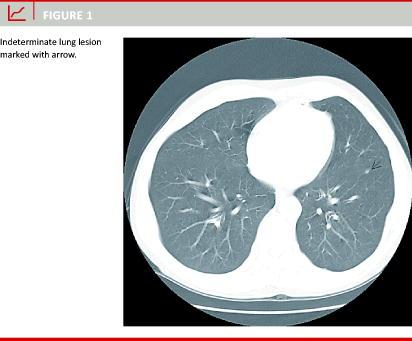

The patients were scanned with a single slice helical scanner (General Electric high-speed CT/i). The slide thickness was 1-10 mm and intravenous contrast was used in all cases. All CT scans were described by expert radiologists. Based on their diagnosis, the patients were grouped into: 1) normal chest CT, 2) manifest lung metastases, 3) suspected malignant lesions, and 4) indeterminate or tentatively benign lesions Figure 1, e.g. fibrotic strand, pleural reaction, calcified nodule etc. These diagnoses were based on the subjective evaluation of at least two experienced radiologists at the time of the examination and not on an exact retrospective grading, as used – among others – by Kronawitter et al [5].